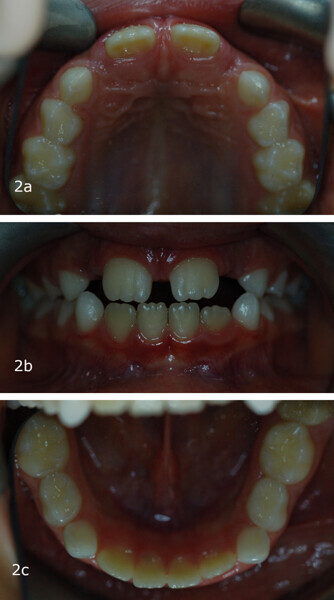

The 8-year-old male patient presented with a diastema between teeth #11 and 21 and non-eruption of teeth #12 and 22 (Fig. 1). The patient underwent a thorough orthodontic examination, including intra-oral photographs, extra-oral photographs, cephalometric radiography of the skull with cephalometric tracing, dental panoramic tomograms, impressions by intra-oral scanning, and functional and phonetic tests. Intra-oral examination (Fig. 2) and pattern analysis showed a Class I molar and canine relationship and contraction of the maxillary arch, displaced pre-contact between teeth #63 and 73, a 3.7 mm diastema between teeth #11 and 21, a mandibular midline deviation to the left, a maxillary midline to the right, and an open bite (−1.5 mm).

Functional analysis showed oronasal breathing, a low tongue posture according to Artese et al. with anterior thrust,21 and consistently leftward-deviating mandibular movements, even in phonetic tests. In these tests, anterior lisp and gliding were present, in addition to lateralisation to the left for articulation.

After 18 months of therapy, a case reassessment was carried out to verify that the goals had all been achieved (Fig. 8). Comparison of extra-oral photographs at the start of treatment (T0) and end of treatment (T1; Fig. 9) showed that excellent balance of the patient’s face had been achieved with a regular, symmetrical smile. Comparison of the intra-oral photographs (Fig. 10) and models (Fig. 11) also showed wider and more harmonious arch forms, closure of the anterior diastema, closure of the open bite and recentring of the mandibular midline. Excellent gingival trophism had also appeared.